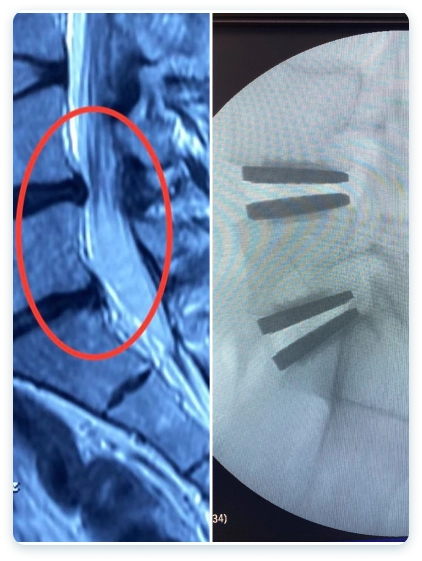

Veja casos de antes e depois dos meus pacientes:

A hérnia de disco lombar ocorre quando o núcleo de um disco intervertebral, que funciona como um amortecedor entre as vértebras, se projeta para fora de seu lugar habitual.

Esta protrusão pode comprimir as raízes nervosas adjacentes ou até mesmo a medula espinhal, resultando em dor, dormência ou fraqueza nas costas e nas pernas.